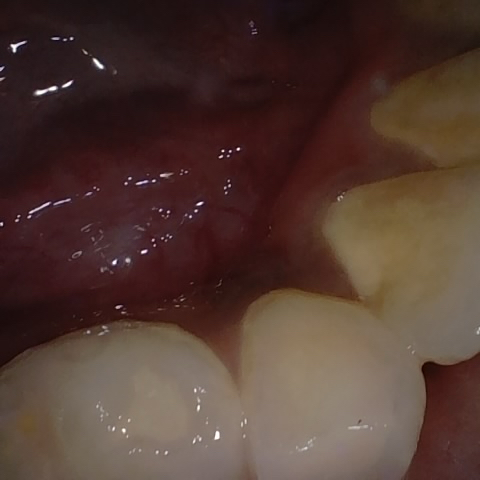

Annotated as "Good"